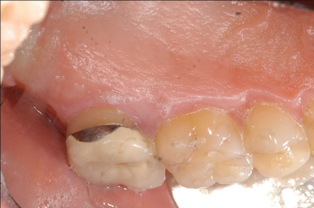

Fig 5. Pre- (Fig 5) and post- (Fig 6) DGV procedure. Note the 7-mm pocket distal to tooth No. 15 before treatment and normal probing depth after treatment. It would have been easier for the restorative dentist to place this crown with increased tooth structure if the tuberosity tissue had been removed previously.

Figure 5

Fig 6. Pre- (Fig 5) and post- (Fig 6) DGV procedure. Note the 7-mm pocket distal to tooth No. 15 before treatment and normal probing depth after treatment. It would have been easier for the restorative dentist to place this crown with increased tooth structure if the tuberosity tissue had been removed previously.

Figure 6

Tuberosity tissue can be harvested using either a distal gingivectomy (DGV) technique12 or distal wedge (DW) technique for CTGs.Calculus is commonly found on the tooth surface (either enamel or root) after the tuberosity harvest. This area must be inspected and scaled and root planed judiciously.

The clinician must determine which of these two harvest techniques should be utilized. Each has its advantages in different situations. For non-wide (buccal-palatal dimension) tuberosities, the DGV technique offers less tissue loss. For wide tuberosities, which are greater than 4 mm in width buccal-lingually and have more CT, the DW technique may be advantageous, as the flap can be approximated and closed with sutures, and this potentially may be more comfortable for the patient. Either technique adequately removes the excess tissue and reduces the pocket. The DGV approach provides a faster tissue harvest and a greater amount of tissue (Figure 5 and Figure 6).